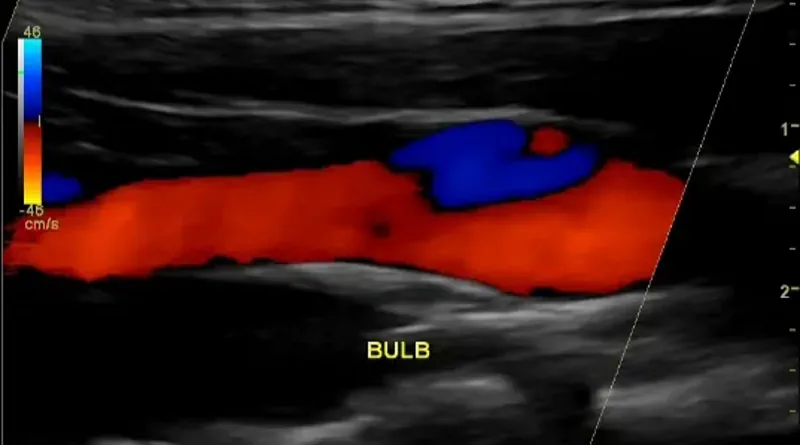

You cannot diagnose a clot in a neck artery without imaging. Imaging means taking pictures of the artery to see if there is a clot. The easiest test is an ultrasound. A carotid artery ultrasound will be able to show blockages in the neck arteries.